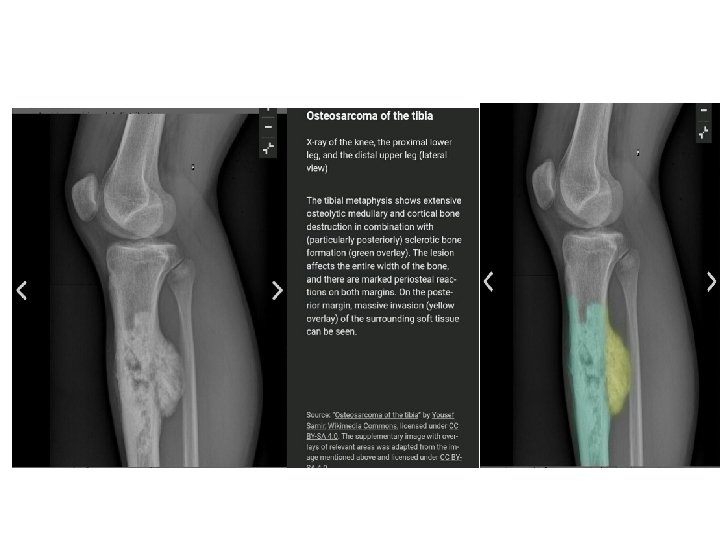

Osteosarcoma Primary osteosarcoma: unknown Secondary osteosarcoma: Paget's disease of bone, radiation injury, bone infarction Incidence: bimodal distribution Primary osteosarcoma: puberty/adolescence Secondary osteosarcoma: advanced age Sex: ♂ > ♀

The sites most commonly involved are the metaphyseal region of long tubular bones, especially the region around knee joint 50% Pain is usually the first symptom; it is constant, worse at night and gradually increases in severity. Sometimes the patient presents with a lump. Pathological fracture is rare. Metastases

Investigations ESR ( raised ) Serum alkaline phosphatase raised X-ray Radioisotope scan skip lesions CT and MRI Chest X-ray done routinely Pulmonary CT ( to R/O metastatic dis. ) Biopsy Bone scan